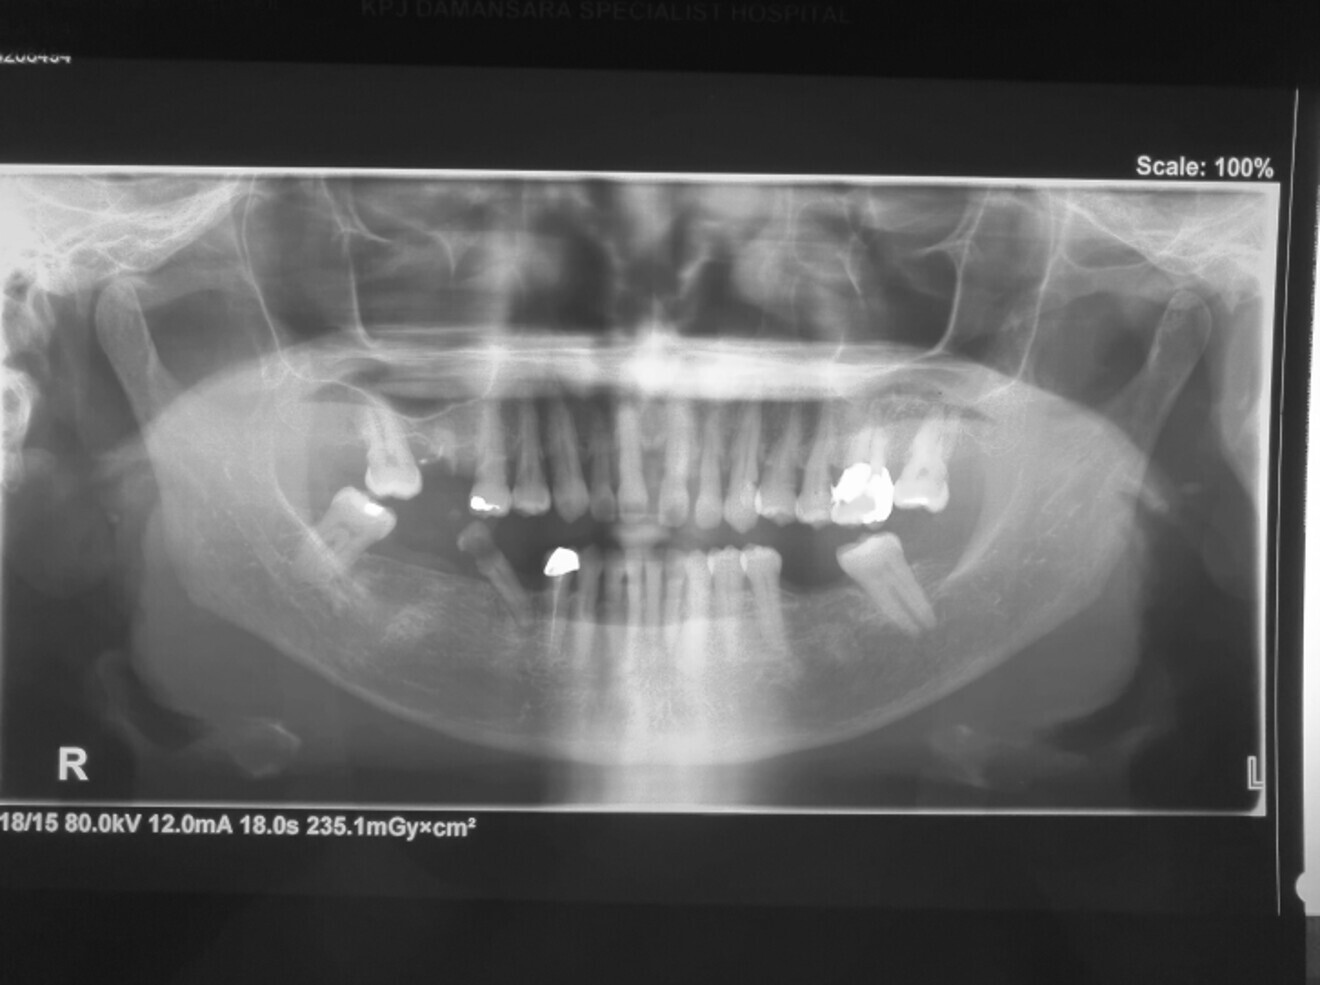

Panoramic radiograph analysis:

Missing 18, 16, 25,26, 28, 36, 47 and 48.

20-30% vertical bone loss upper anterior region.